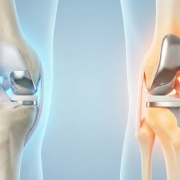

تعویض مفصل زانو یا آرتروپلاستی

تعویض مفصل زانو یا آرتروپلاستی (Arthroplasty) ، عمل تعویض مفصل زانو است که طی آن مفصل آسیب دیده بیمار بطور کامل جایگزین می گردد. یکی از رایج ترین عللی که باعث می شود که بیماران برای تعویض مفصل زانو اقدام کنند ، درد شدید زانو ، ناشی از آسیب ، تصادف ،بیماری های مزمن و …ادامهی مطلب »